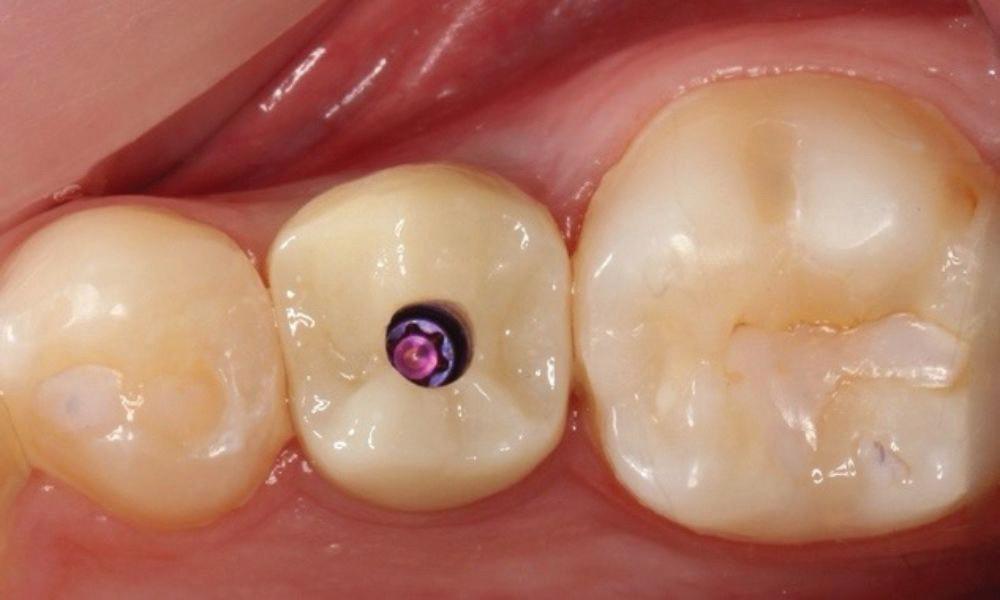

With the increasing use of all ceramics within practice, a clinician must under stand adhesive procedures to ensure adequate bond strength for predictability and longevity. Clearfil ceramic primer plus is a single com ponent adhesive primer used to enhance bond strength between resin-based materials, as well as porcelain, composite, hybrid ceramics, metal oxide (zirconia) and lithium disilicate. It contains the adhesive phosphate containing monomer (MDP) used for adhesive bonding as well as to metal oxide. Additionally, it contains a silane cou pling agent which guarantees strong adhesion to all glass-based ceramic materials. It is a one bottle system meaning there is no mixing and has excellent shelf life compared to other silanes which need to have careful storage.

Estelite Asteria (Tokuyama)One of my favourite composite resin materials is Asteria which is a light-cured radiopaque composite for universal use. It considerably simplifies multilayer techniques yet delivers outstanding aesthetics with excellent polishability. Unlike mul tilayer techniques used with conventional composites, Asteria uses only 2 layers for optimal results without compromising aesthetics. The microstructure of the material produces a light diffusion that helps blend in with the natural tooth structure. The chameleon like nature of the material allows a blending of the materials to natural tooth structure and it allows excellent polishability which retains its lustre over time.